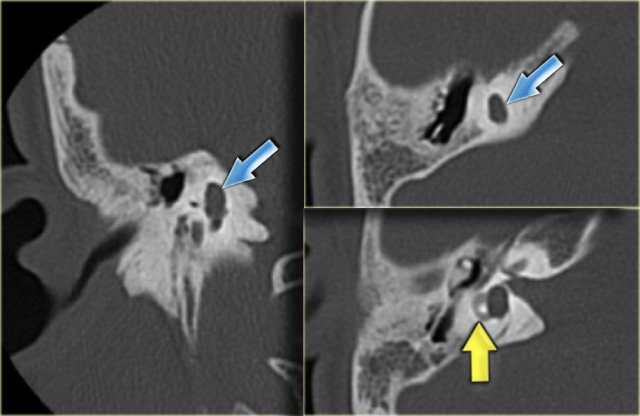

Dehiscent jugular bulb

On the left a dehiscent jugular bulb (blue arrow).

This can be dangerous during myringotomy.

Note also the bulging sigmoid sinus (yellow arrow).